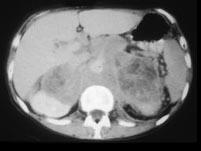

问题 男,76岁,全身浅表淋巴结肿大,请结合下列图片作出诊断 ( )

选项 A、肾上腺转移瘤 B、肾上腺淋巴瘤 C、肾上腺癌 D、肾上腺嗜铬细胞瘤 E、肾上腺腺瘤

答案 B